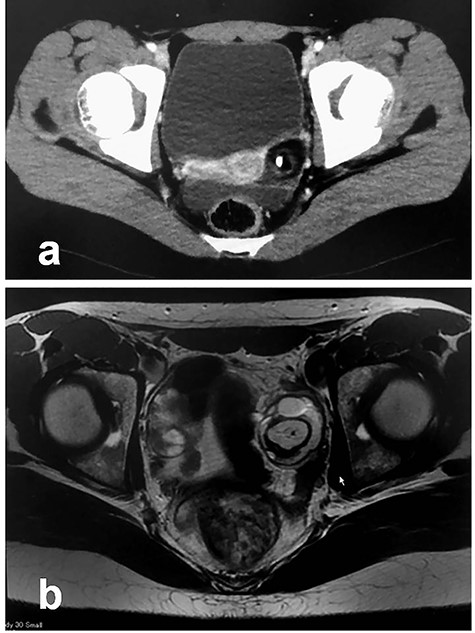

Patient 2: In a 14-year-old girl with abdominal pain, enhanced CT showed a left ovarian tumor (Fig. 3a). Further examination, including MRI, revealed an ovarian MCT (70 cm × 67 cm; Fig. 3b). She underwent laparoscopic surgery, during which the tumor was placed in a specimen retrieval bag. The contents were aspirated using a newly developed soft-cup aspirator set (Hakko Co., Tokyo, Japan) [9], and the tumor was excised without content spillage (Fig. 4). The excised margins were continuously oversewn using the V-Loc™ absorbable wound closure device (Covidien Healthcare, Minneapolis, MN). Pathologic examination confirmed the diagnosis of MCT. She has been doing well without evidence of recurrence. She subsequently established a regular menstrual cycle.